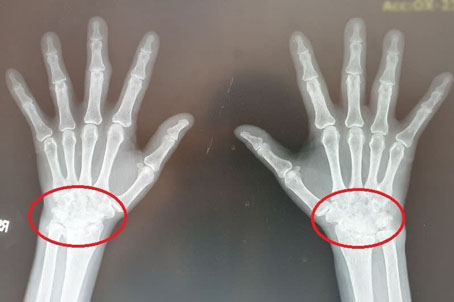

医师抽血发现,刘小姐类风湿因子和发炎指数过高,且手部X光片已发现骨骼结构破坏及变形,手腕动作受限,确诊“类风湿性关节炎”,于是替她申请重大伤病证明。经过药物治疗,刘女士病情控制稳当,疼痛改善,发炎指数也恢复正常,目前正常生活。

诊断类风湿性关节炎的方式包含症状评估、抽血检视类风湿因子和发炎指数,以及利用超音波、X光等影像检查确认关节是否变形、发炎。颜忆宁指出,类风湿性关节炎以药物治疗为主,包含口服类固醇、免疫调节抗风湿药物、小分子药物以及注射生物制剂,并视关节损伤程度予以关节复健或关节置换手术、肌腱缝补等手术治疗。